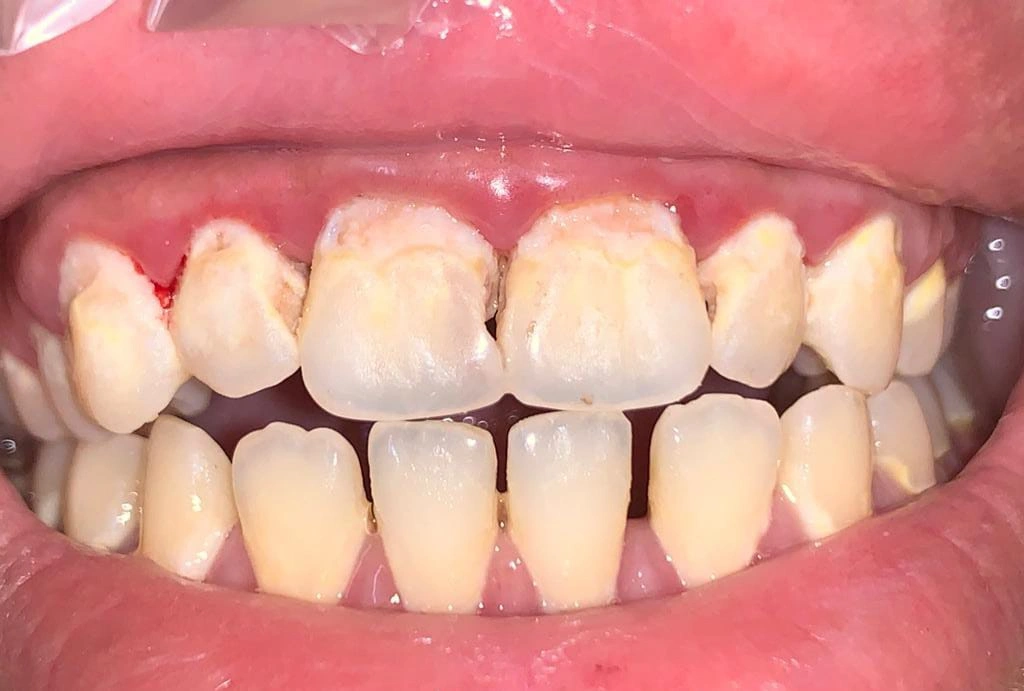

Clinical Cases